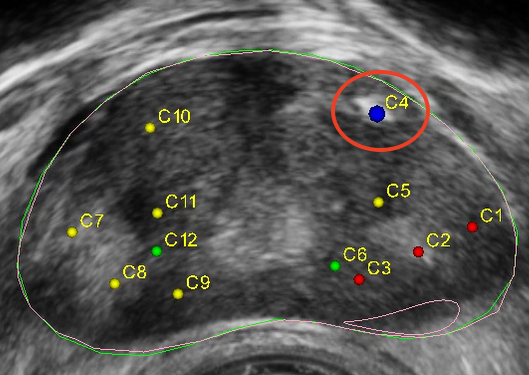

▲穿刺靶點(diǎn)

本次手術(shù)患者近日因身體不適到院檢查,進(jìn)行血清前列腺特異性抗原(PSA)篩查,結(jié)果顯示數(shù)值偏高,穿刺手術(shù)指癥明顯。在與患者及家屬溝通后牛少曦教授決定為患者行前列腺穿刺活檢術(shù),他表示,前列腺癌發(fā)病癥狀隱蔽,早期沒(méi)有任何癥狀,病灶不易被發(fā)現(xiàn),且與前列腺增生的臨床表現(xiàn)相似,往往會(huì)被患者、臨床醫(yī)生疏漏。在臨床,不少患者一經(jīng)發(fā)現(xiàn)已是晚期,治療棘手,嚴(yán)重的影響了患者預(yù)后。

牛少曦教授表示,Mona Lisa通過(guò)智能軟件制定方案,輔助臨床醫(yī)生更好地完成各項(xiàng)操作,不僅具備3D可視化MRI-超聲融合技術(shù),且其運(yùn)動(dòng)補(bǔ)償和針偏移位置補(bǔ)償技術(shù)也進(jìn)一步提高了穿刺手術(shù)的精準(zhǔn)性,解決了人工前列腺穿刺活檢時(shí)精準(zhǔn)度低、穿刺不均勻、并發(fā)癥較高等多種痛點(diǎn)。在MonaLisa的輔助下,臨床醫(yī)生可以更安全、精確、智能、高效地進(jìn)行活檢取樣,減少漏診率,減少穿刺針數(shù),減輕患者痛苦。該技術(shù)的推廣,將為男性前列腺惡性腫瘤疾病的精準(zhǔn)診斷和早篩提供技術(shù)支持,推動(dòng)提高了醫(yī)院前列腺穿刺操作技術(shù)水平,為前列腺癌患者帶來(lái)了福音。